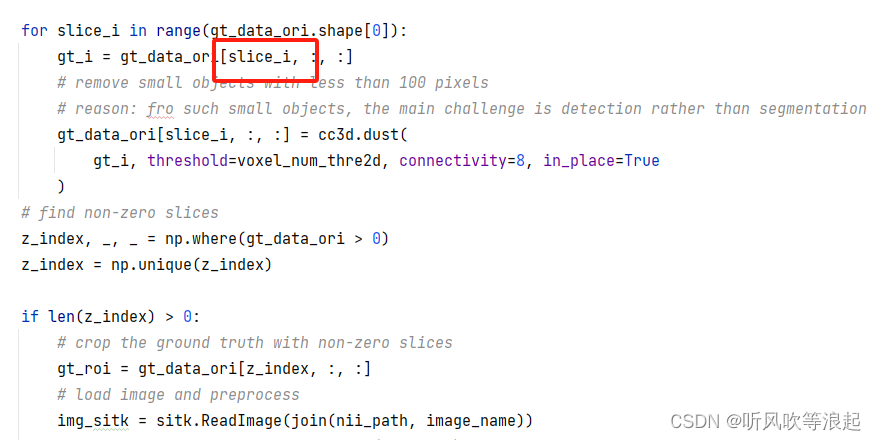

5.3.1 切片成2D数据,并且剔除小部分的数据

MedSAM项目如下,这里明显只是对3D数据的横断面进行切分,最后保存成2D数据

3D数据的格式是【a,b,c】 这里的abc都很大

而非[a,b,3]这种颜色堆叠的rgb图像

而nii.gz 数据往往是医学的3D数据,换句话说,每个通道都是灰度的

而因为人体瘦长的缘故,沿着横断面切,效果是最好的,要不然数据会出现窄长的不均衡比例(瞎猜的)

之前本人写切片的时候,也会去除前景区域不足的数据,这里给了解释

换而言之,小区域是目标检测的任务,而非分割的重点!!

而这里设定的100,和我们之前设定的比例0.01之类的效果差不多